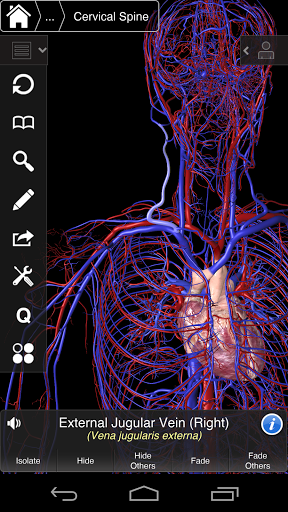

Essential Anatomy 3 reprezentuje najnowsze przełomowe technologie 3D i innowacyjny design. Najnowocześniejszy silnik graficzny 3D, zbudowany na zamówienie przez 3D4Medical od podstaw, zapewnia bardzo dokładny model anatomiczny i zapewnia doskonałą jakość grafiki, której żaden inny konkurent nie jest w stanie osiągnąć.

Aplikacja przedstawia unikalne podejście do uczenia się ogólnej anatomii. Grafika jest nieporównywalna i sprawia, że uczenie się, dzięki wykorzystaniu treści informacyjnej i innowacyjnych funkcji, jest bogatym i wciągającym doświadczeniem.

Ta aplikacja zawiera niezbędną anatomię dla 10 systemów:

⁃Żyły

⁃Artyki

⁃Nerwowość

Essential Anatomy 3 jest responsywny, wizualnie oszałamiający i pozbawiony wysiłku. Aplikacja jest w pełni 3D, co oznacza, że możesz zobaczyć dowolną strukturę anatomiczną w izolacji, a także pod dowolnym kątem.

---- Ponad 4000 bardzo szczegółowych struktur anatomicznych